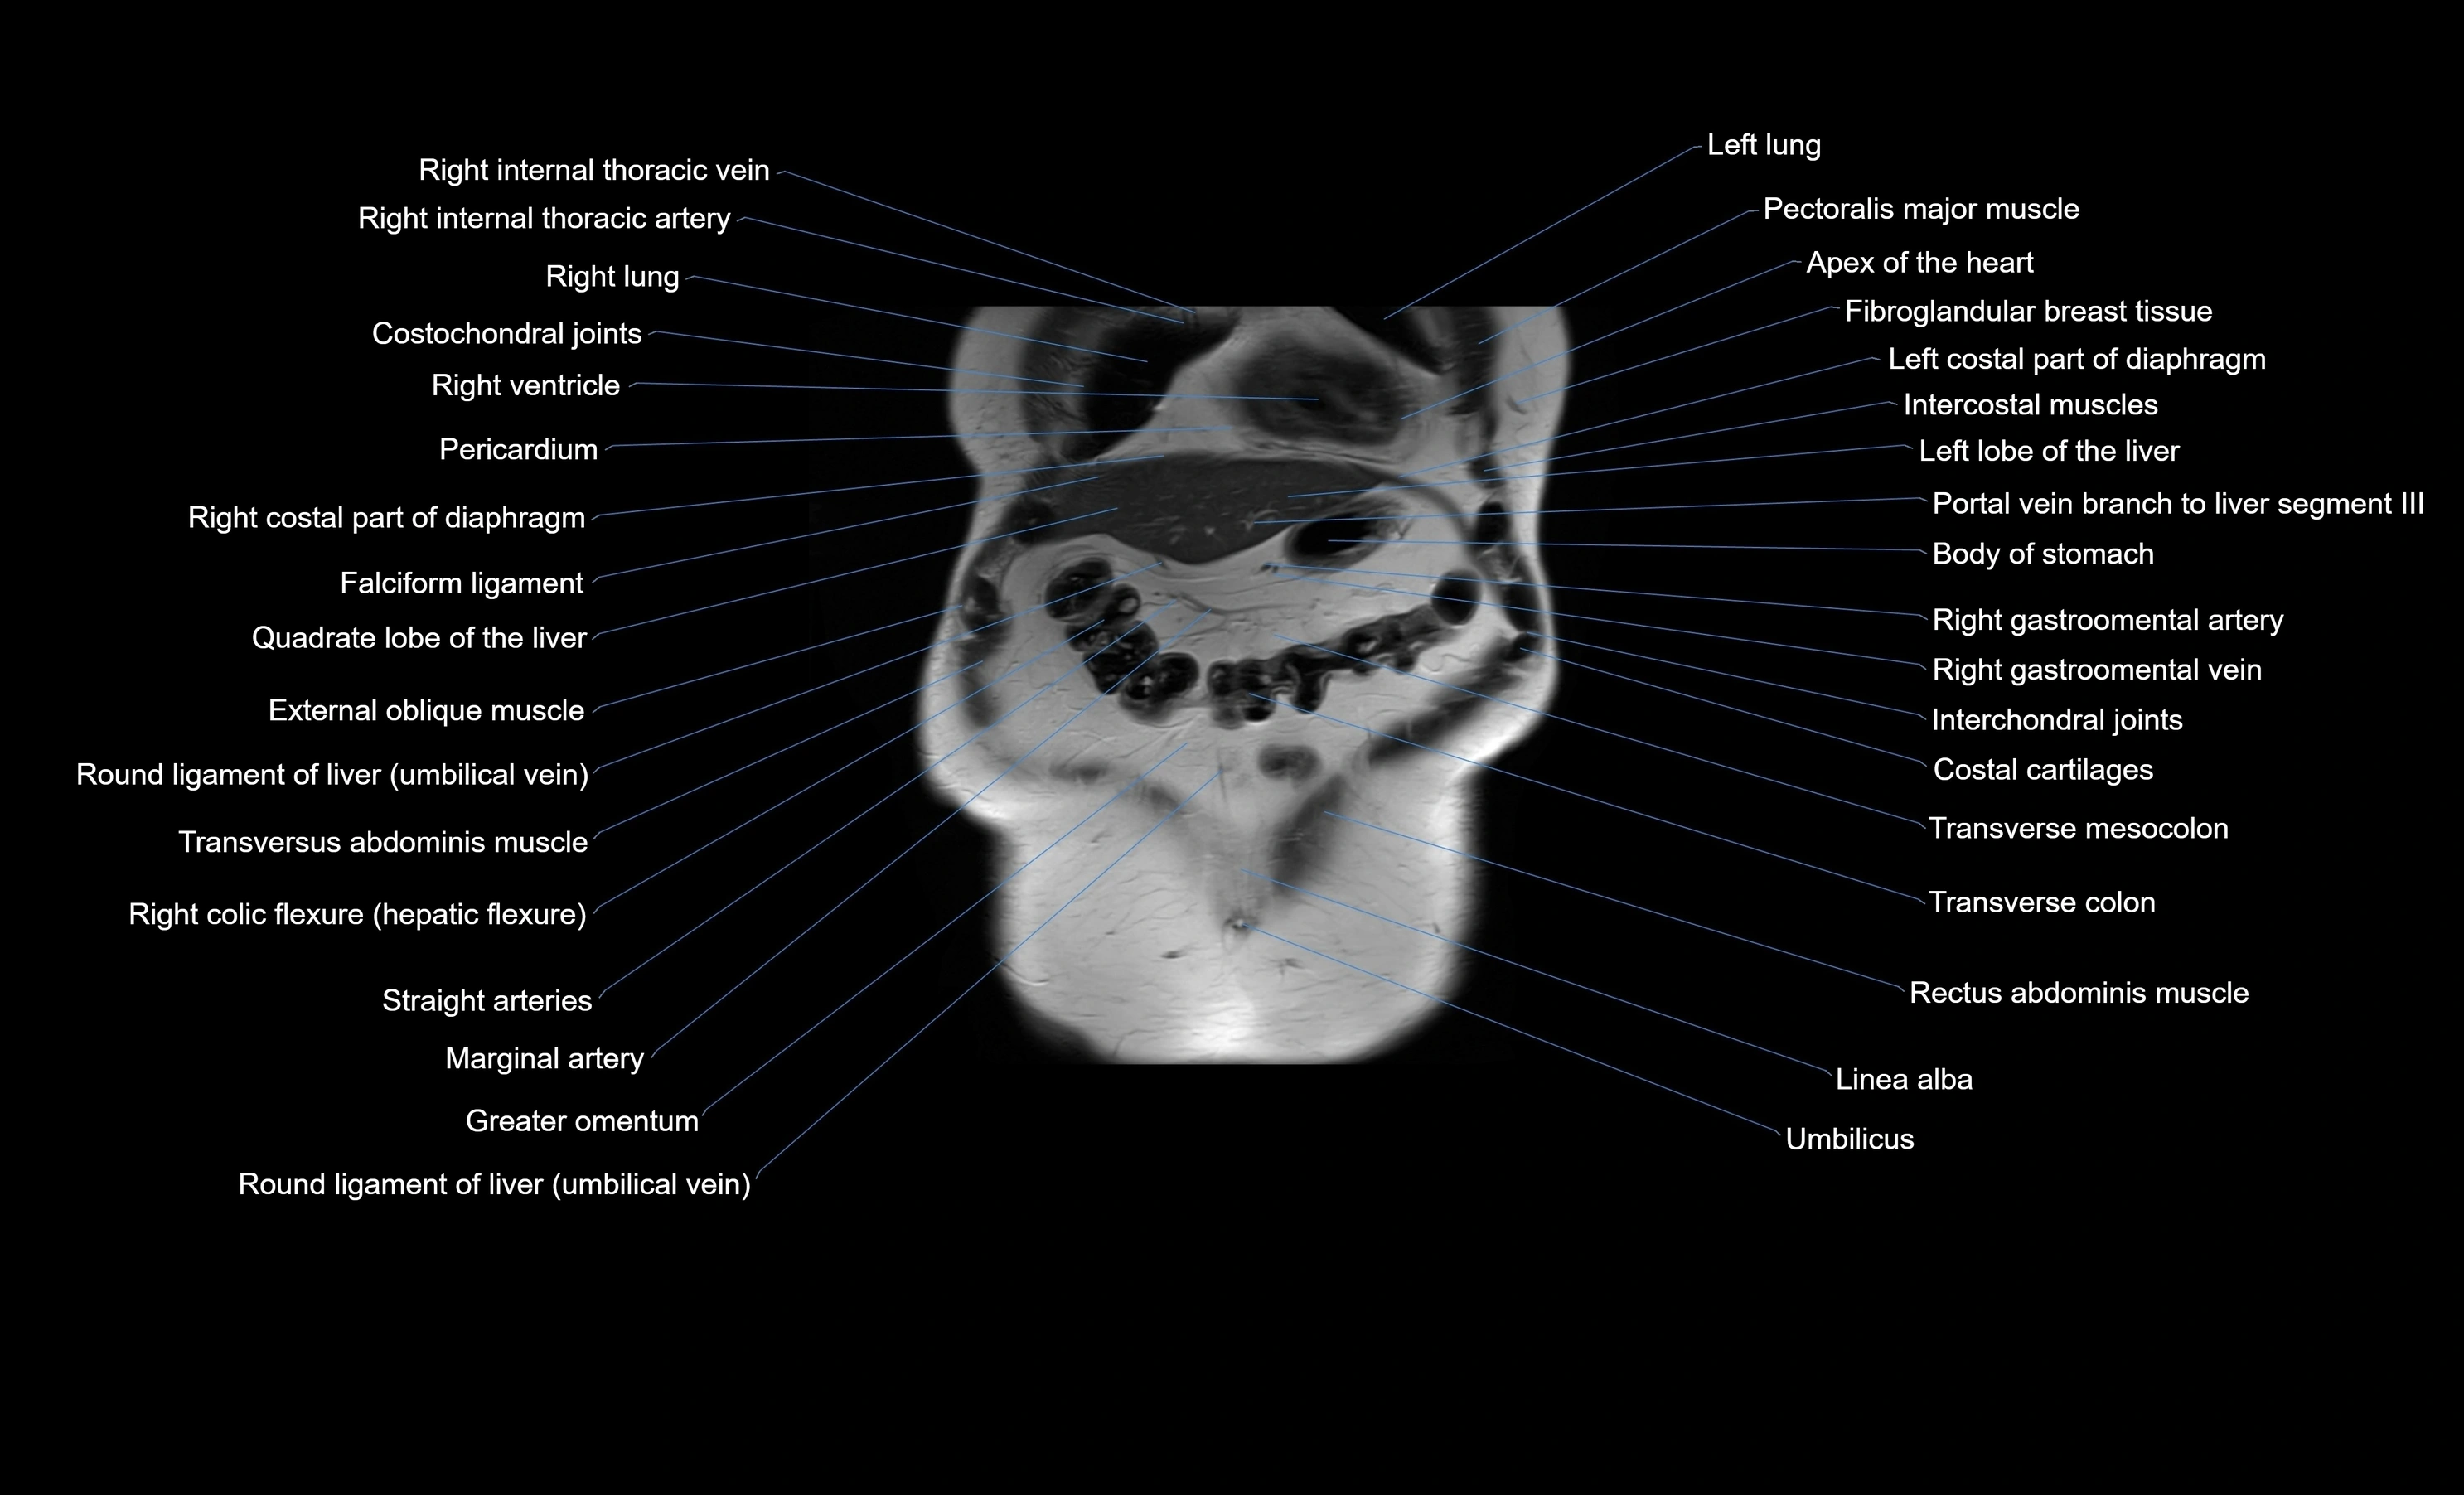

MRI images